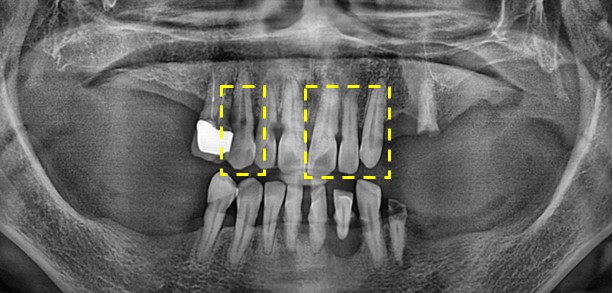

먼저 초진 구강 사진을 보도록 하겠습니다.

위의 사진으로 보시다 싶이 구강관리가 전혀 되지 않아 치석과 치태들이 쌓여 잇몸도 녹아 내렸으며

썩어서 뿌리만 겨우 남은 치아들까지 있으셨습니다. 전체적으로 매우 좋지 않은 상태입니다.

표시된 #13 #21 22 23 치아들은 신경치료후 크라운 치료를

나머지 구치부 치아들은 임플란트 치료를 진행하였습니다.

치아들이 썩어 자연스럽게 소실 되시면서 잇몸뼈들도 많이 녹아 내린 상태였습니다

전체적으로 뼈 이식 이후 임플란트 치료를 진행하였습니다.